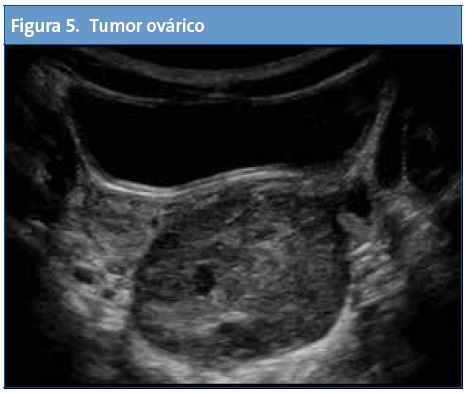

En Atención Primaria el mayor rendimiento se obtiene de la exploración abdominal seguida del estudio de la zona cervical, partes blandas, aparato genital, pulmón y aparato locomotor.